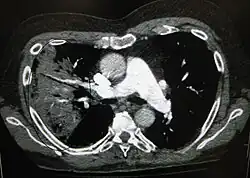

A CT scan can give additional information in indeterminate cases[42] and provide more details in those with an unclear chest radiograph (for example occult pneumonia in chronic obstructive pulmonary disease). They can be used to exclude pulmonary embolism and fungal pneumonia, and detect lung abscesses in those who are not responding to treatments.[41] However, CT scans are more expensive, have a higher dose of radiation, and cannot be done at bedside.[41]